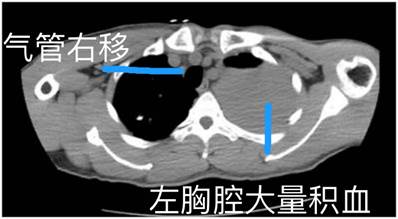

迅速接诊的胸心外科吴再义副主任医师,在快速进行检查后发现,锋利的水果刀从左侧第五肋间刺入文先生的胸腔,左侧胸腔大量积血,气管受压向右侧移位,心包内有积液,当即考虑刀刺伤心脏的可能性很大。心脏刀刺伤是胸心外科十分凶险的急危重症,其病死率极高,仅有10%左右的伤者能及时被送到医院急救,绝大多数患者往往在极短时间内因心脏骤停、心脏压塞或创伤失血性休克死于现场附近。